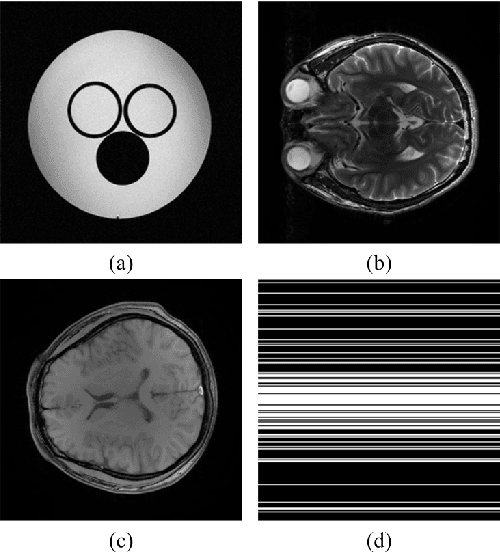

Abstract:Objective: Improve the reconstructed image with fast and multi-class dictionaries learning when magnetic resonance imaging is accelerated by undersampling the k-space data. Methods: A fast orthogonal dictionary learning method is introduced into magnetic resonance image reconstruction to providing adaptive sparse representation of images. To enhance the sparsity, image is divided into classified patches according to the same geometrical direction and dictionary is trained within each class. A new sparse reconstruction model with the multi-class dictionaries is proposed and solved using a fast alternating direction method of multipliers. Results: Experiments on phantom and brain imaging data with acceleration factor up to 10 and various undersampling patterns are conducted. The proposed method is compared with state-of-the-art magnetic resonance image reconstruction methods. Conclusion: Artifacts are better suppressed and image edges are better preserved than the compared methods. Besides, the computation of the proposed approach is much faster than the typical K-SVD dictionary learning method in magnetic resonance image reconstruction. Significance: The proposed method can be exploited in undersapmled magnetic resonance imaging to reduce data acquisition time and reconstruct images with better image quality.